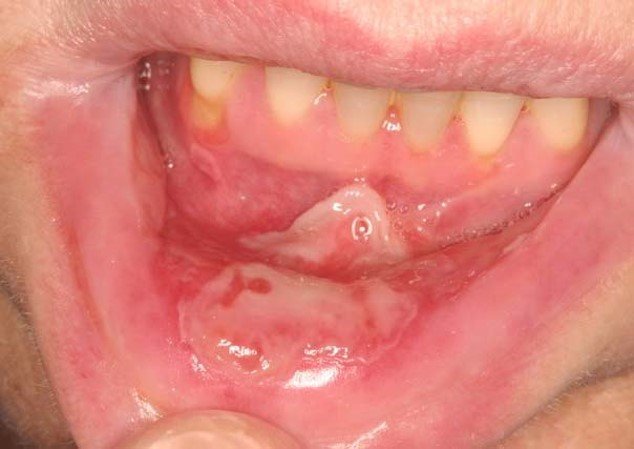

Oral mucositis is a severely debilitating condition characterized by erythema, edema, and ulcerations of the oral mucosa.

Evaluating for oral mucositis is dependent upon clinical history and physical exam findings. Laboratory and radiography are not as helpful. If ulcers are present on the hard palate, attached gingiva, or tongue dorsum, cultures should be obtained to rule out viral or fungal etiology.